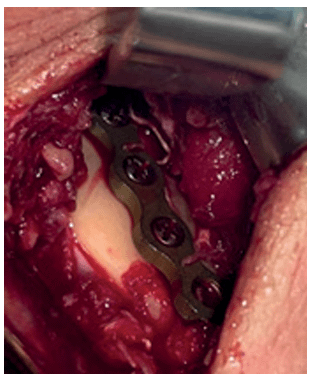

24 horas después de su llegada al centro hospitalario se colocaron Arcos barra de Erich, para obtener una oclusión en máxima intercuspidación y estabilidad de los segmentos mientras era llevado a sala de operaciones Tres días después fue llevado a sala de operaciones por cirugía maxilofacial.. Con anestesia general, intubación nasotraqueal se procedió a realizar asepsia-antisepsia con Hibitane y se infiltró lidocaína más epinefrina 1:100000 2 cartuchos de 1.8 ml cada uno en cada abordaje quirúrgico como hemostático selectivo. Se hizo el marcaje quirúrgico para, mediante técnica tunelizada, realizar abordajes retromandibulares y acceder a segmentos óseos no comprometidos como ángulo y rama mandibular derecha y abordaje submandibular izquierdo a nivel de parasínfisis mandibular izquierda. Cabe mencionar que hubo orificio de entrada y salida de la bala, cada herida de aproximadamente 1 cm, fue lavada y debridada al ingresar al centro hospitalario.

Imagen 2. Se puede observar oclusión dental en máxima intercuspidación durante la cirugía.

Una vez realizados los abordajes se colocó la tracción interdentomaxilar y se procedió a tunelizar el tejido sobre el músculo para poder pasar la placa de reconstrucción, la cual se moldeó y fue una placa de sistema 2.4 Osteomed, se fijó con tres tornillos sistema 2.4 en cada extremo considerando la distancia de 1 cm alejados del trazo de fractura.

Imagen 3. Abordaje y fijación en rama mandibular derecha

Imagen 4. Abordaje y fijación en parasínfisis mandibular izquierda

Se procedió a suturar con vicryl 3/0 cada plano muscular y piel se cerró con Nylon 5/0.